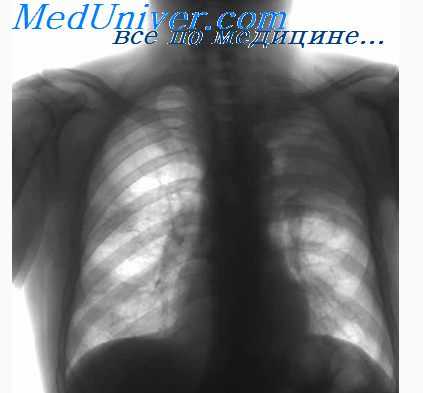

· Рентгенологическое обследование органов грудной клетки (состояние медиастинальных лимфатических узлов, легочной ткани, плевры), включая компьютерную томографию.

- Лимфогранулематоз [болезнь Годжкина (Hodgkin)]. Лимфогранулематоз корней легких может быть одно- и двусторонним. При двусторонней локализации лимфатические узлы при лимфогранулематозе поражены не столь симметрично, как при туберкулезе или при саркоидозе, так что уже сама асимметрия при резко очерченных прикорневых узлах заставляет думать о лимфогранулематозе. Поставить диагноз по клинической картине чрезвычайно трудно, если нет увеличения других лимфатических узлов (аксиллярных, надключичных, вдоль грудино-ключично-сосковой мышцы) или селезенки. Лимфогранулематоз следует предполагать в том случае, если имеются лихорадка интермиттирующего типа (Пель—Эбштейн) и в крови значительная лимфопения (лимфоцитоз почти исключает лимфогранулематоз) и эозинофилия. Однако, если поражены только отдельные узлы, лимфопении и эозинофилии может не быть. Диагноз лимфогранулематоза решает гистологическое исследование. Поэтому необходимо всегда делать пробную биопсию, если узел легко доступен. При соответствующей опытности хирурга биопсия не сопряжена с опасностью, даже если берется прикорневой узел. Прежде чем производить биопсию прикорневого узла, безусловно необходимо раньше прибегнуть к значительно более безобидному вмешательству — пробной биопсии по Daniels. Она проводится на лимфатических узлах, которые всегда имеются в жировой ткани позади места прикрепления m. sternocleidomastoideus на высоте места прикрепления m. scalenus anterior к I ребру. Особенно ценна эта биопсия при лимфогранулематозе (Lageze с сотрудниками). Положительные результаты мы имели также при туберкулезе и бронхогенном раке.